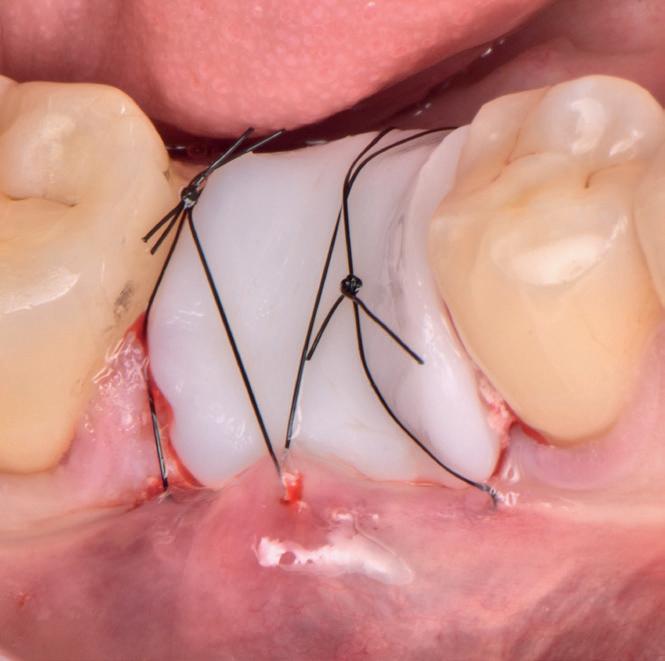

Elemental Antibacterial Wound Dressing

A Revolution in Bone Graft Protection

Minimise Complications and Improve Healing Conditions In Mucogingival and Implant Surgery

Leveraging the antibacterial and wound-healing properties of zinc ions, Elemental can be used post-operatively with or without a membrane.

Elemental activates when in contact with boiling water, and the resulting material, which sets rigid and stable, can be quickly and easily moulded and shaped according to the needs of the patient.